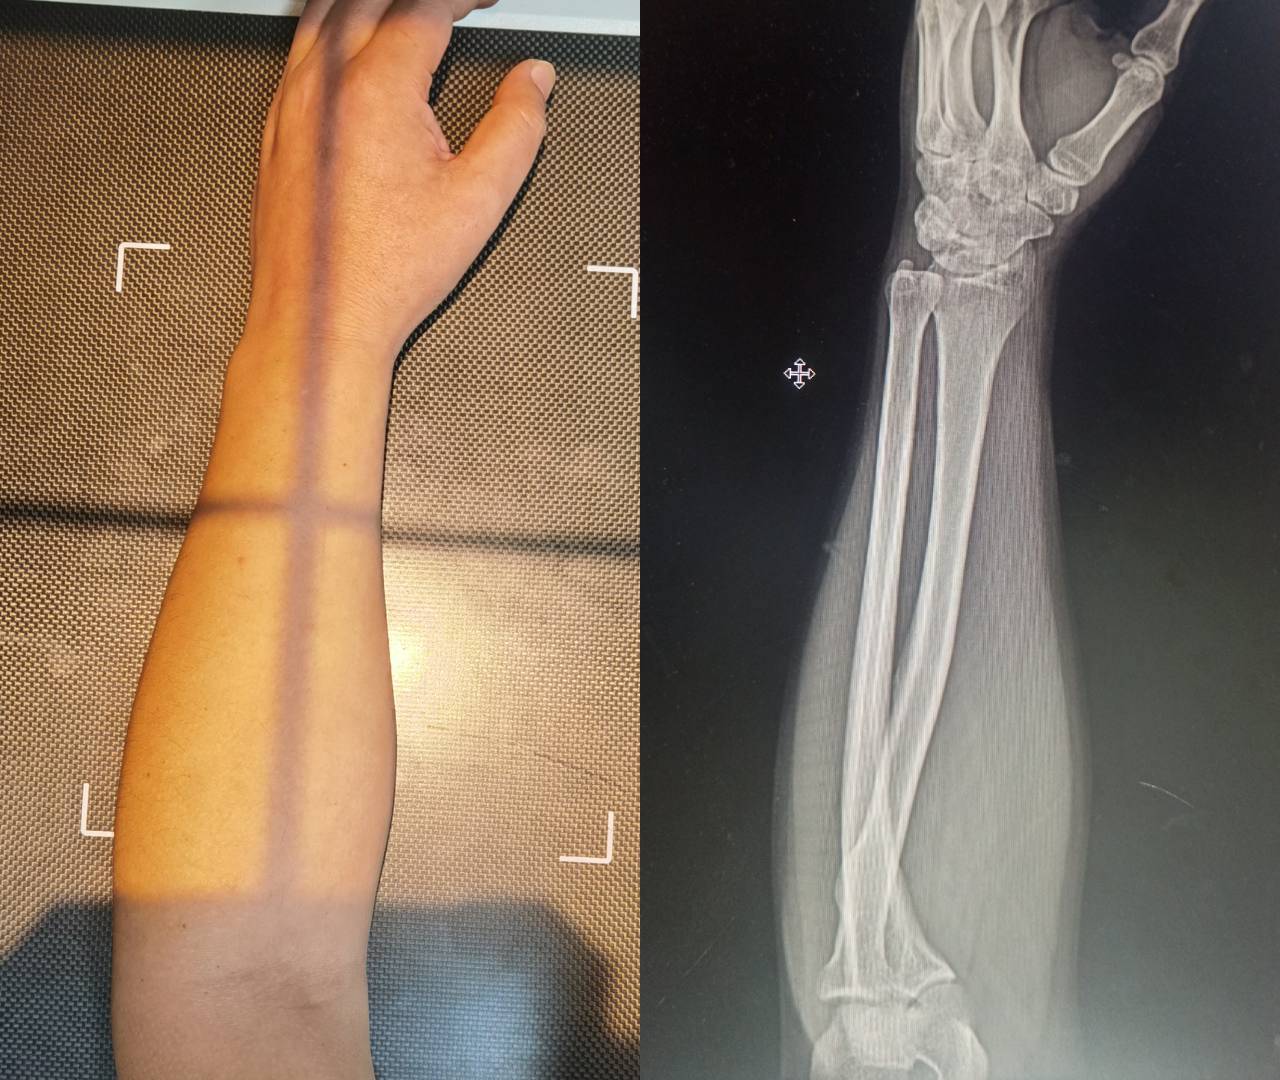

Ordered the Nature version with red switches,which does exactly as advertised. Eliminated wrist pain and reduced the size of a developing ganglion cyst(within 3 weeks) .